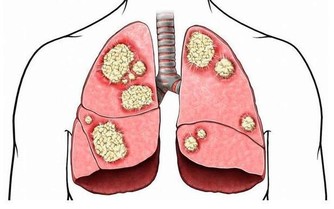

鱉又名甲魚、團魚、元魚、水魚、腳魚等。現代藥理研究,鱉甲可以調節免疫功能,提高淋巴細胞的轉化率,使抗體存在時間延長,增進骨髓造血功能,保護腎上腺皮質功能,防止細胞癌變。臨床實踐證明,吃鱉肉對防治肝癌、腦腫瘤、肺癌、惡性淋巴瘤、胃癌、鼻咽癌和乳腺癌等有一定的作用。